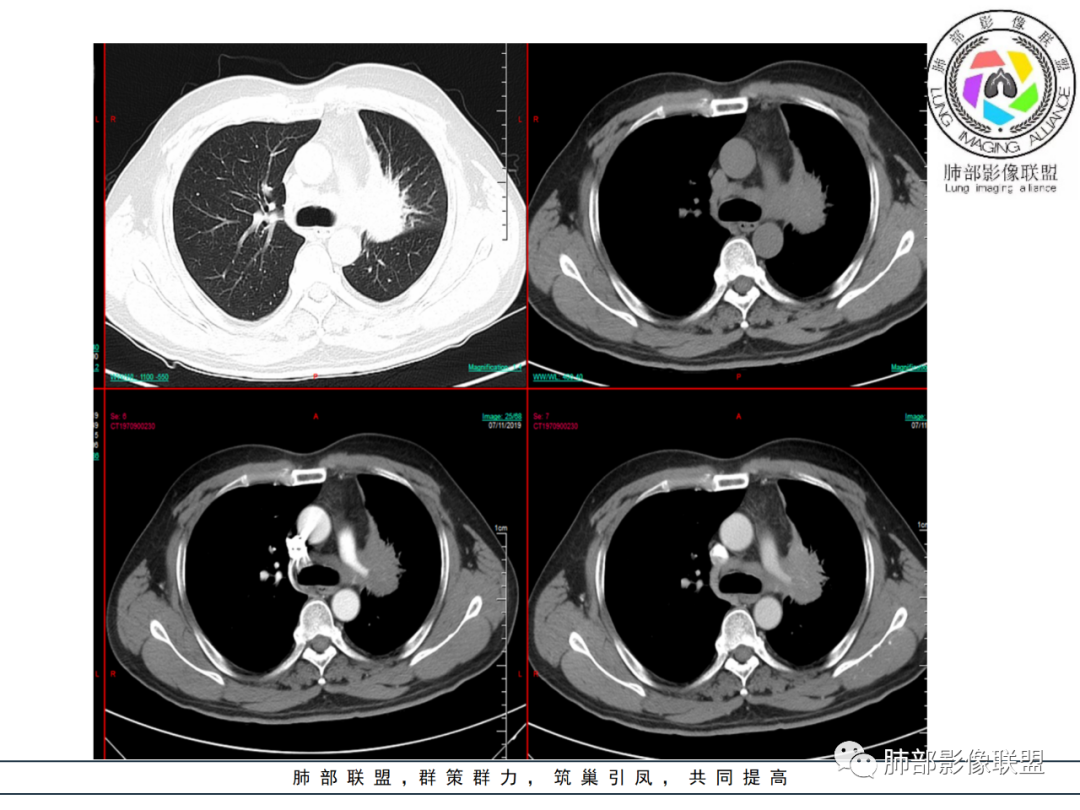

中年男性,左肺肺门区占位伴肺不张,上叶尖段气管外压性狭窄,增强病灶未见明显坏死。首先定性还是恶性,病灶未见明显坏死,周围毛刺分叶都有,首先考虑腺癌可能性大。 医学百科网 | YxBaike.Com

老年男性,细胞角质蛋白19片段指标偏高,左肺门软组织密度影,左肺上叶支气管开口狭窄,增强可见肺动脉受压,纵隔内见肿大淋巴结影,考虑鳞癌 医学百科网 | YxBaike.Com

左肺上叶体积缩小,透光度减低,局部肺不张,左肺门肿块,左肺上叶支气管被包绕呈鼠尾状狭窄,左肺主动脉被包绕受侵犯,纵隔内多发肿大淋巴结,左肩胛骨周围软组织内多发针状钙化,首先定恶性,考虑1小细胞肺癌2腺癌 医学百科网 | YxBaike.Com

中年男性 左肺门软组织肿块,包绕支气管呈鼠尾状狭窄,远端少许阻塞性改变,增强扫描肺门血管受压变性,肿块均匀强化,未见明显强化,肿块向肺门纵隔延伸,肺门纵隔脂肪分界不清。诊断,恶性占位,男性肺门肿块鳞癌需要考虑,但是没有湖泊坏死,没有明显阻塞性改变;小细胞,纵隔淋巴结没有明显融合,但是肺门侧有融合冰冻表现,不能排除。另外病灶边缘分叶、毛刺形成,强化均匀,猜一个腺鳞癌不除外。最后诊断 小细胞或腺鳞癌

患者中年男性,咳嗽、咳痰1月余,同时伴有胸闷不适。胸CT:左肺上叶占位并膨胀不全,左肺上叶支气管支气管不规则狭窄,左肺固有上叶开口呈鼠尾状闭塞。纵隔窗:4L 4R 6 7 左肺门淋巴结肿大,增强静脉期较动脉期强化,血管包埋,左肺下叶肺动脉纤细。

左肺门肿块,支气管壁增厚狭窄,增强均匀强化,叶间胸膜受压,纵膈多发结节,隆突下多发结节,考虑淋巴瘤。鉴别小细胞肺癌、腺癌、鳞癌。 医学百科网 | YxBaike.Com

中年男性,咳嗽咳痰1月余。左肺门肿块,包绕肺门血管支气管,血管、支气管受压、变细、阻塞,破坏不明显。强化较均匀,未见明显坏死区。左肺体积减小,前段不张,中央间质增厚。纵隔、左肺门多发肿大淋巴结、部分融合。考虑恶性病变,淋巴瘤?小细胞癌?

左肺门软组织肿块,包绕左主、左上叶支气管及分支,变窄,前段支气管闭塞,局限肺不张,左肺动脉受压,轻度强化,纵隔淋巴结增大,考虑肺癌,小细胞癌可能。 医学百科网 | YxBaike.Com

临床及影像所见:

1.中年男性,咳嗽咳痰一月余,无咯血。 医学百科网 | YxBaike.Com

2.左肺上叶肺门区见不规则块影,前方边界不可分。主动脉窗结节影边界稍模糊且与肺门块影融为一体。密度均匀,未见钙化及液化。相邻肺血管影轻度受压。

3.左肺上叶前段支气管及其分支狭窄闭塞。 医学百科网 | YxBaike.Com

左肺上叶舌段重度狭窄并见腔内软组织影突入。 医学百科网 | YxBaike.Com

注意,支气管的狭窄或闭塞是多处多段的! 医学百科网 | YxBaike.Com

4.左肺上叶体积缩小,其中前段不张并萎陷纵隔旁。

5.肺门块影及不张肺组织均轻到中度强化,未衬托出低密度块影。

6.隆突下见增大淋巴结,环形强化为主。 医学百科网 | YxBaike.Com

7.纵隔左移(而非纵隔冻结)。提示病程漫长或存在相关基础疾病。

8.左肩胛骨旁动脉期血管影显示,疑逆流或回流受阻。扫描范围内肩胛骨及肋骨等未见明显骨质吸收破坏。